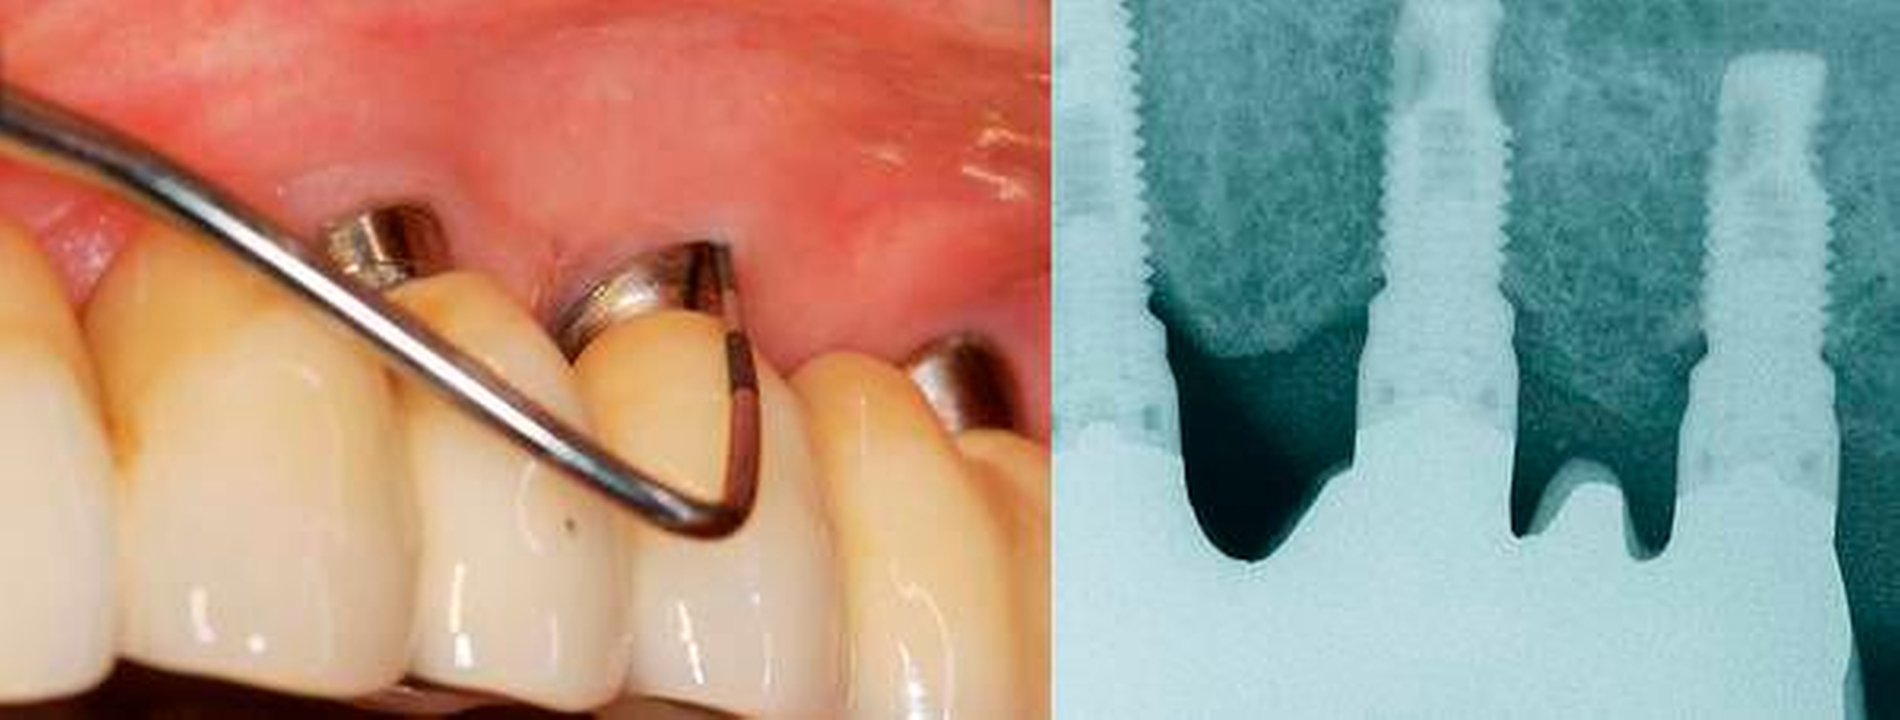

Peri-implantitis ist ein Plaque-assoziierter pathologischer Zustand, der in den Geweben um Zahnimplantate herum auftritt. Er ist durch eine Entzündung in der peri-implantären Mukosa und den Verlust an Implantat-tragendem Knochen gekennzeichnet. Stellen mit Peri-implantitis zeigen klinische Entzündungszeichen einschließlich Blutungen bei Sondierung und/oder Eiterung, erhöhte Sondierungstiefen und/oder eine Rezession des Mukosarandes und röntgenologischen Knochenverlust im Vergleich zu früheren Untersuchungen. Peri-Implantitis-Läsionen erstrecken sich nach apikal des Saum-/Taschenepithels und sind größer als diejenigen an Stellen mit peri-implantärer Mukositis und Parodontitis.

Falldefinition der Peri-implantitis in der täglichen klinischen Praxis:

- Blutung und/oder Eiterung bei sanfter Sondierung

- Erhöhte Sondierungstiefe im Vergleich zu früheren Untersuchungen

- Knochenabbau

Die Falldefinition der Peri-implantitis beinhaltet BOP und Knochenabbau.

In Ermangelung früherer Untersuchungsdaten kann die Diagnose einer Peri-implantitis basieren auf der Kombination von:

- Sondierungstiefen von größer/gleich 6 mm

- Knochenniveau größer/gleich 3 mm apikal des am weitesten koronal befindlichen Abschnitts des intraossären Implantatanteils.